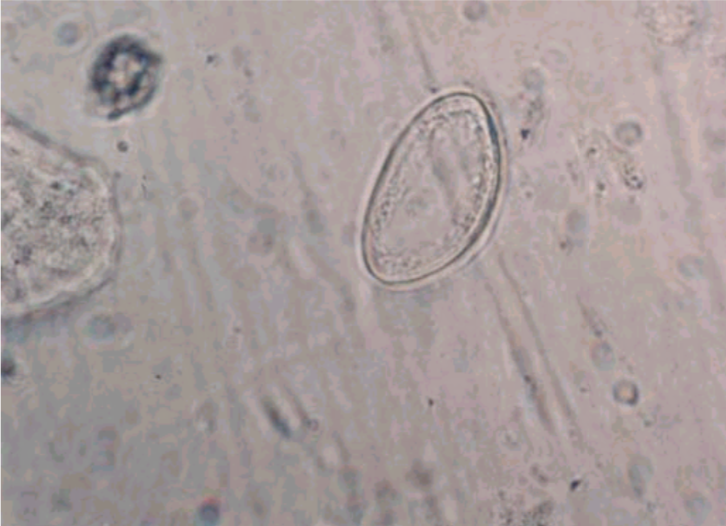

Enterobius vermicularis eggs